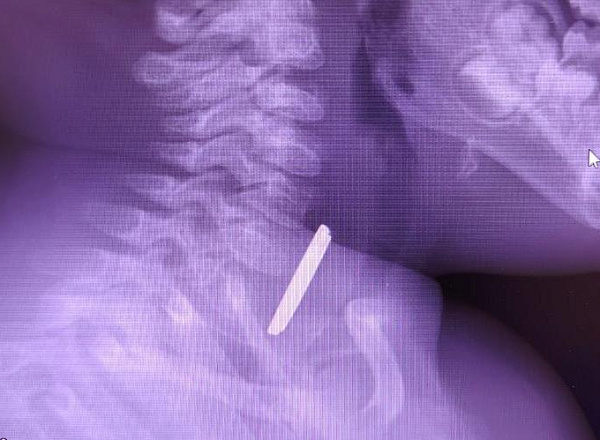

В Нижневартовске хирурги спасли годовалого ребенка, проглотившего батарейку

В Нижневартовске врачи окружной детской больницы провели успешную операцию по спасению жизни годовалого малыша, проглотившего батарейку. Ребенок поступил в медучреждение с симптомами затрудненного глотания и повышенного слюнотечения. Об этом сообщили в Департаменте здравоохранения ХМАО-Югры. Как сообщил врач-детский хирург Вячеслав Воронин, на рентгеновском снимке было обнаружено инородное тело в пищеводе. В ходе экстренной операции батарейку извлекли, однако она успела вызвать глубокий электрохимический ожог, занявший половину просвета пищевода. После операции и курса интенсивной терапии в реанимации состояние ребенка стабилизировалось. При контрольном обследовании врач отметил положительную динамику заживления без признаков осложнений. Малыш был выписан домой на амбулаторное лечение.